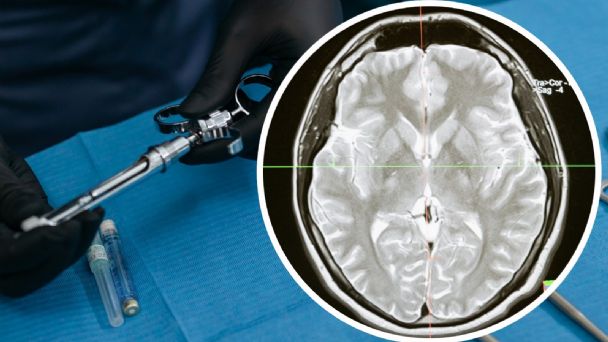

Oficialmente se ha confirmado el primer caso de meningitis en Matamoros, Tamaulipas, justo una semana después de que se notificara a las autoridades sobre un posible brote. La paciente afectada será trasladada a la Ciudad de México para recibir atención especializada en el hospital México Siglo XXI del Seguro Social.

El secretario de Salud de Tamaulipas, Vicente Joel Hernández Navarro, informó que, de los tres pacientes identificados en México, solo se ha confirmado el padecimiento en esta mujer, quien fue internada en el Hospital Número Tres de Matamoros. Los otros dos pacientes están siendo atendidos en clínicas particulares y también reciben atención de infectólogos.